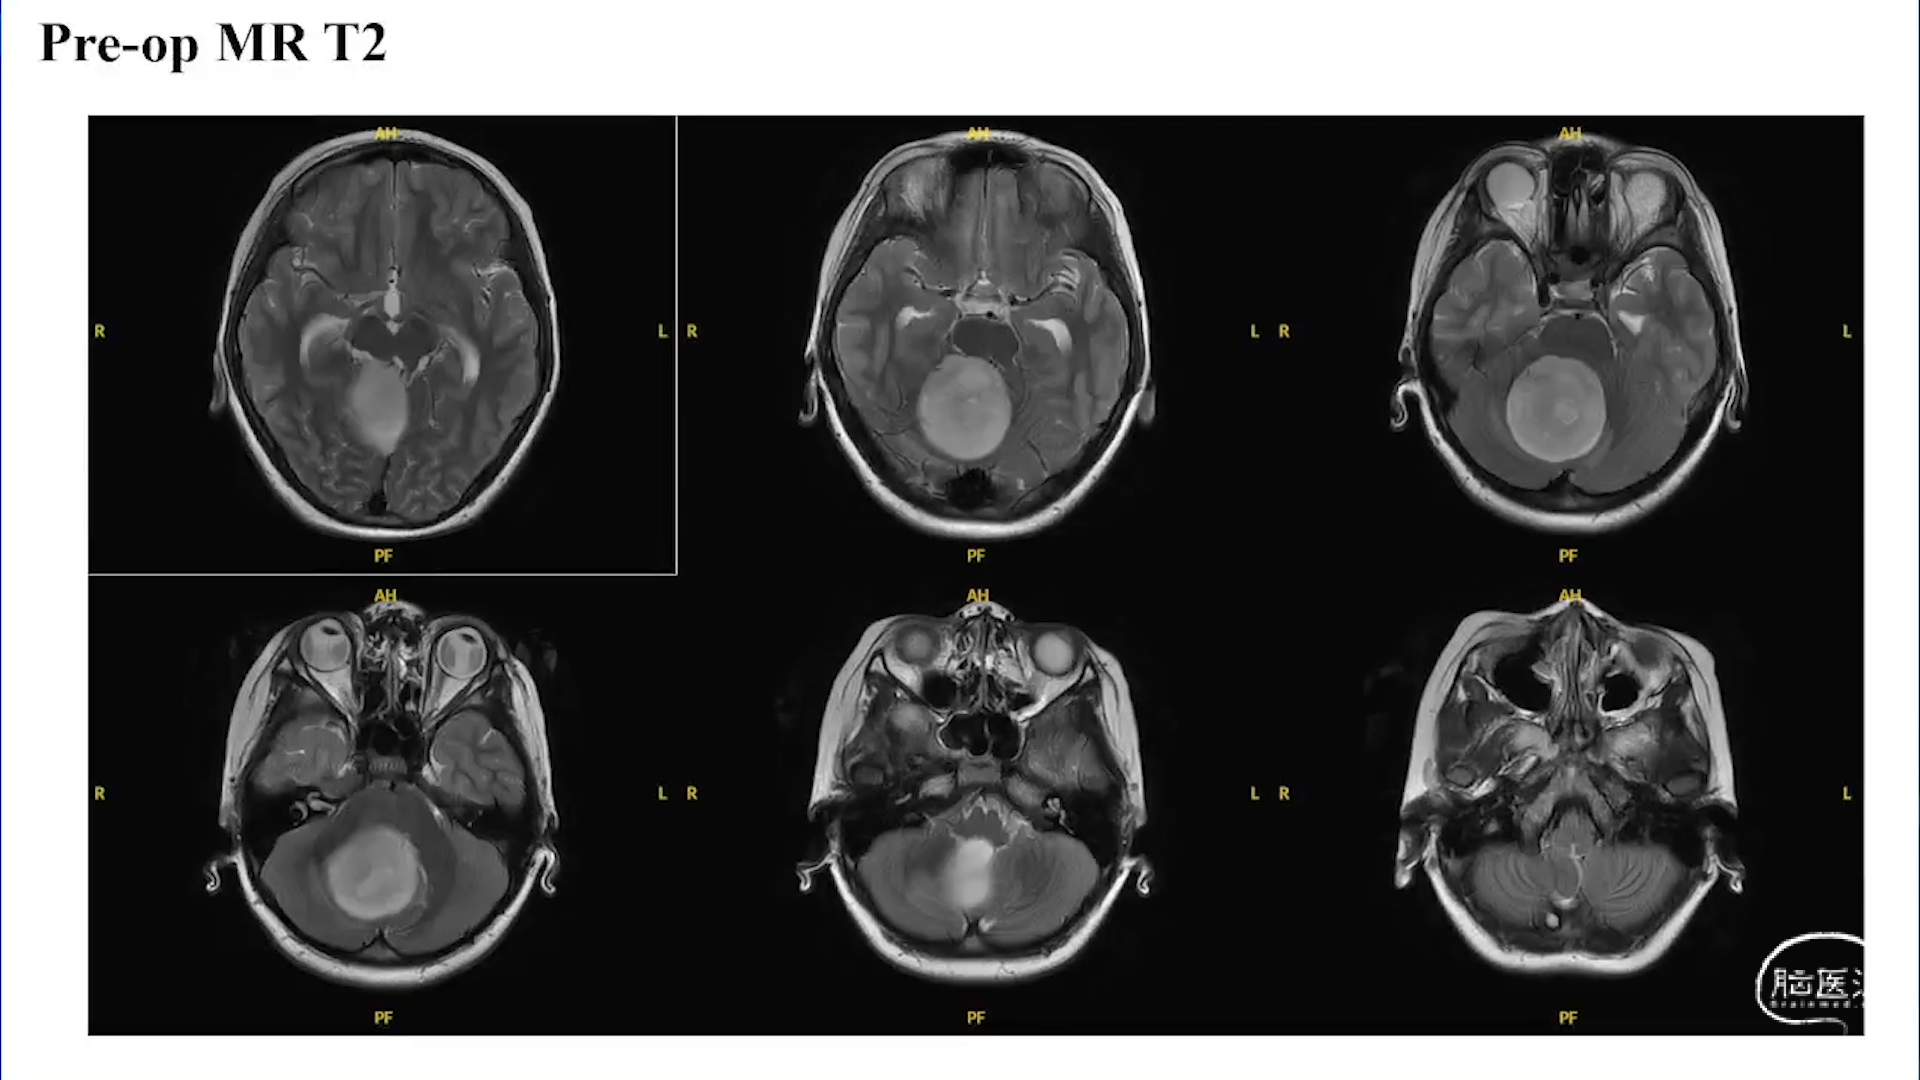

小脑星形细胞肿瘤